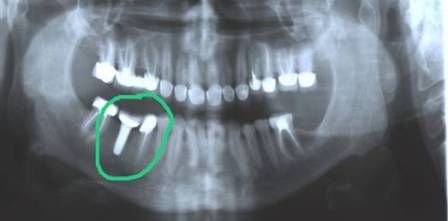

Endosteal implantlar - bu implantlar, cerrahi yöntemle, çene kemiğine direkt olarak implante edilirler. Çevredeki dişeti dokusu iyileştikten sonra, orijinal implanta bağlantı sağlayacak materyali takmak için ikinci bir operasyon gerekir. Son olarak, yapay diş (veya dişler) tek başına veya köprü ya da protez üzerinde grup halinde implanta takılır.